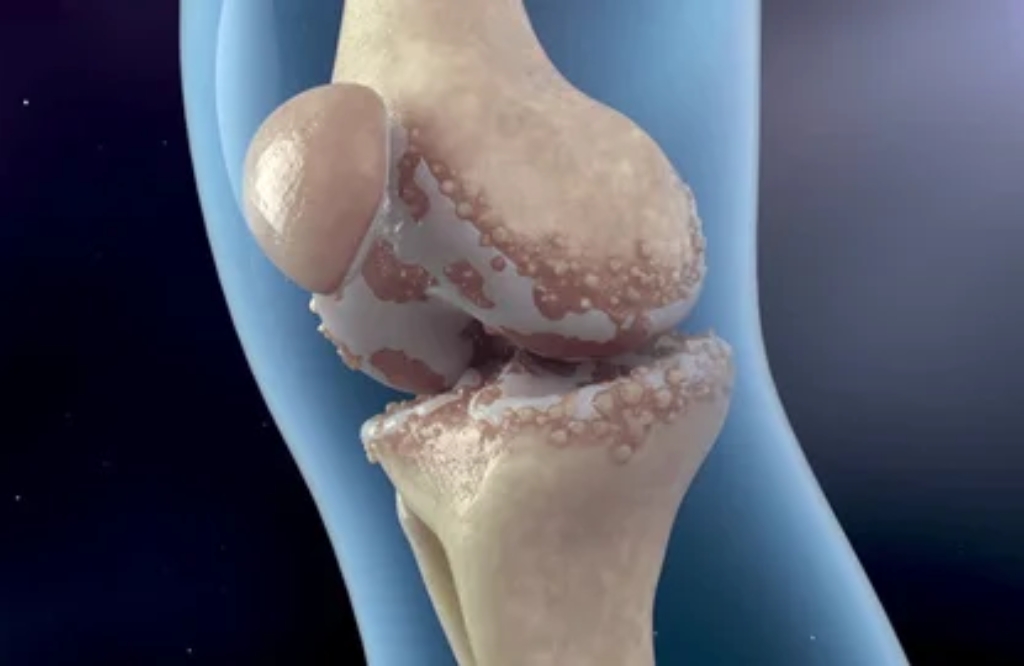

A artrose é uma condição degenerativa das articulações que causa dor, rigidez e limitações nos movimentos. Com o passar do tempo, a cartilagem que reveste as articulações vai se desgastando, comprometendo a mobilidade e causando desconforto nas atividades diárias. Esse problema é comum em pessoas com mais de 50 anos, mas também pode afetar pessoas mais jovens devido a lesões ou predisposição genética.

A artrose pode afetar diversas articulações do corpo, como os joelhos, quadris, coluna e mãos, dificultando o simples ato de caminhar, subir escadas ou até segurar objetos. O tratamento adequado pode ajudar a controlar os sintomas, retardar a progressão da doença e melhorar a qualidade de vida do paciente.